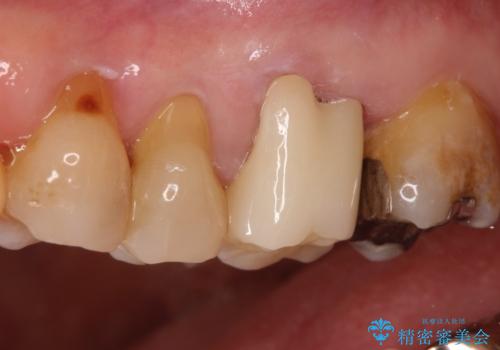

発見の難しい虫歯。根管治療から被せもの治療

- 定期検診にて被せものと歯との隙間に虫歯を発見した患者様です。

根管治療から被せもの治療(ベレッツァ)まで行いました。(根管治療は林院長に依頼)